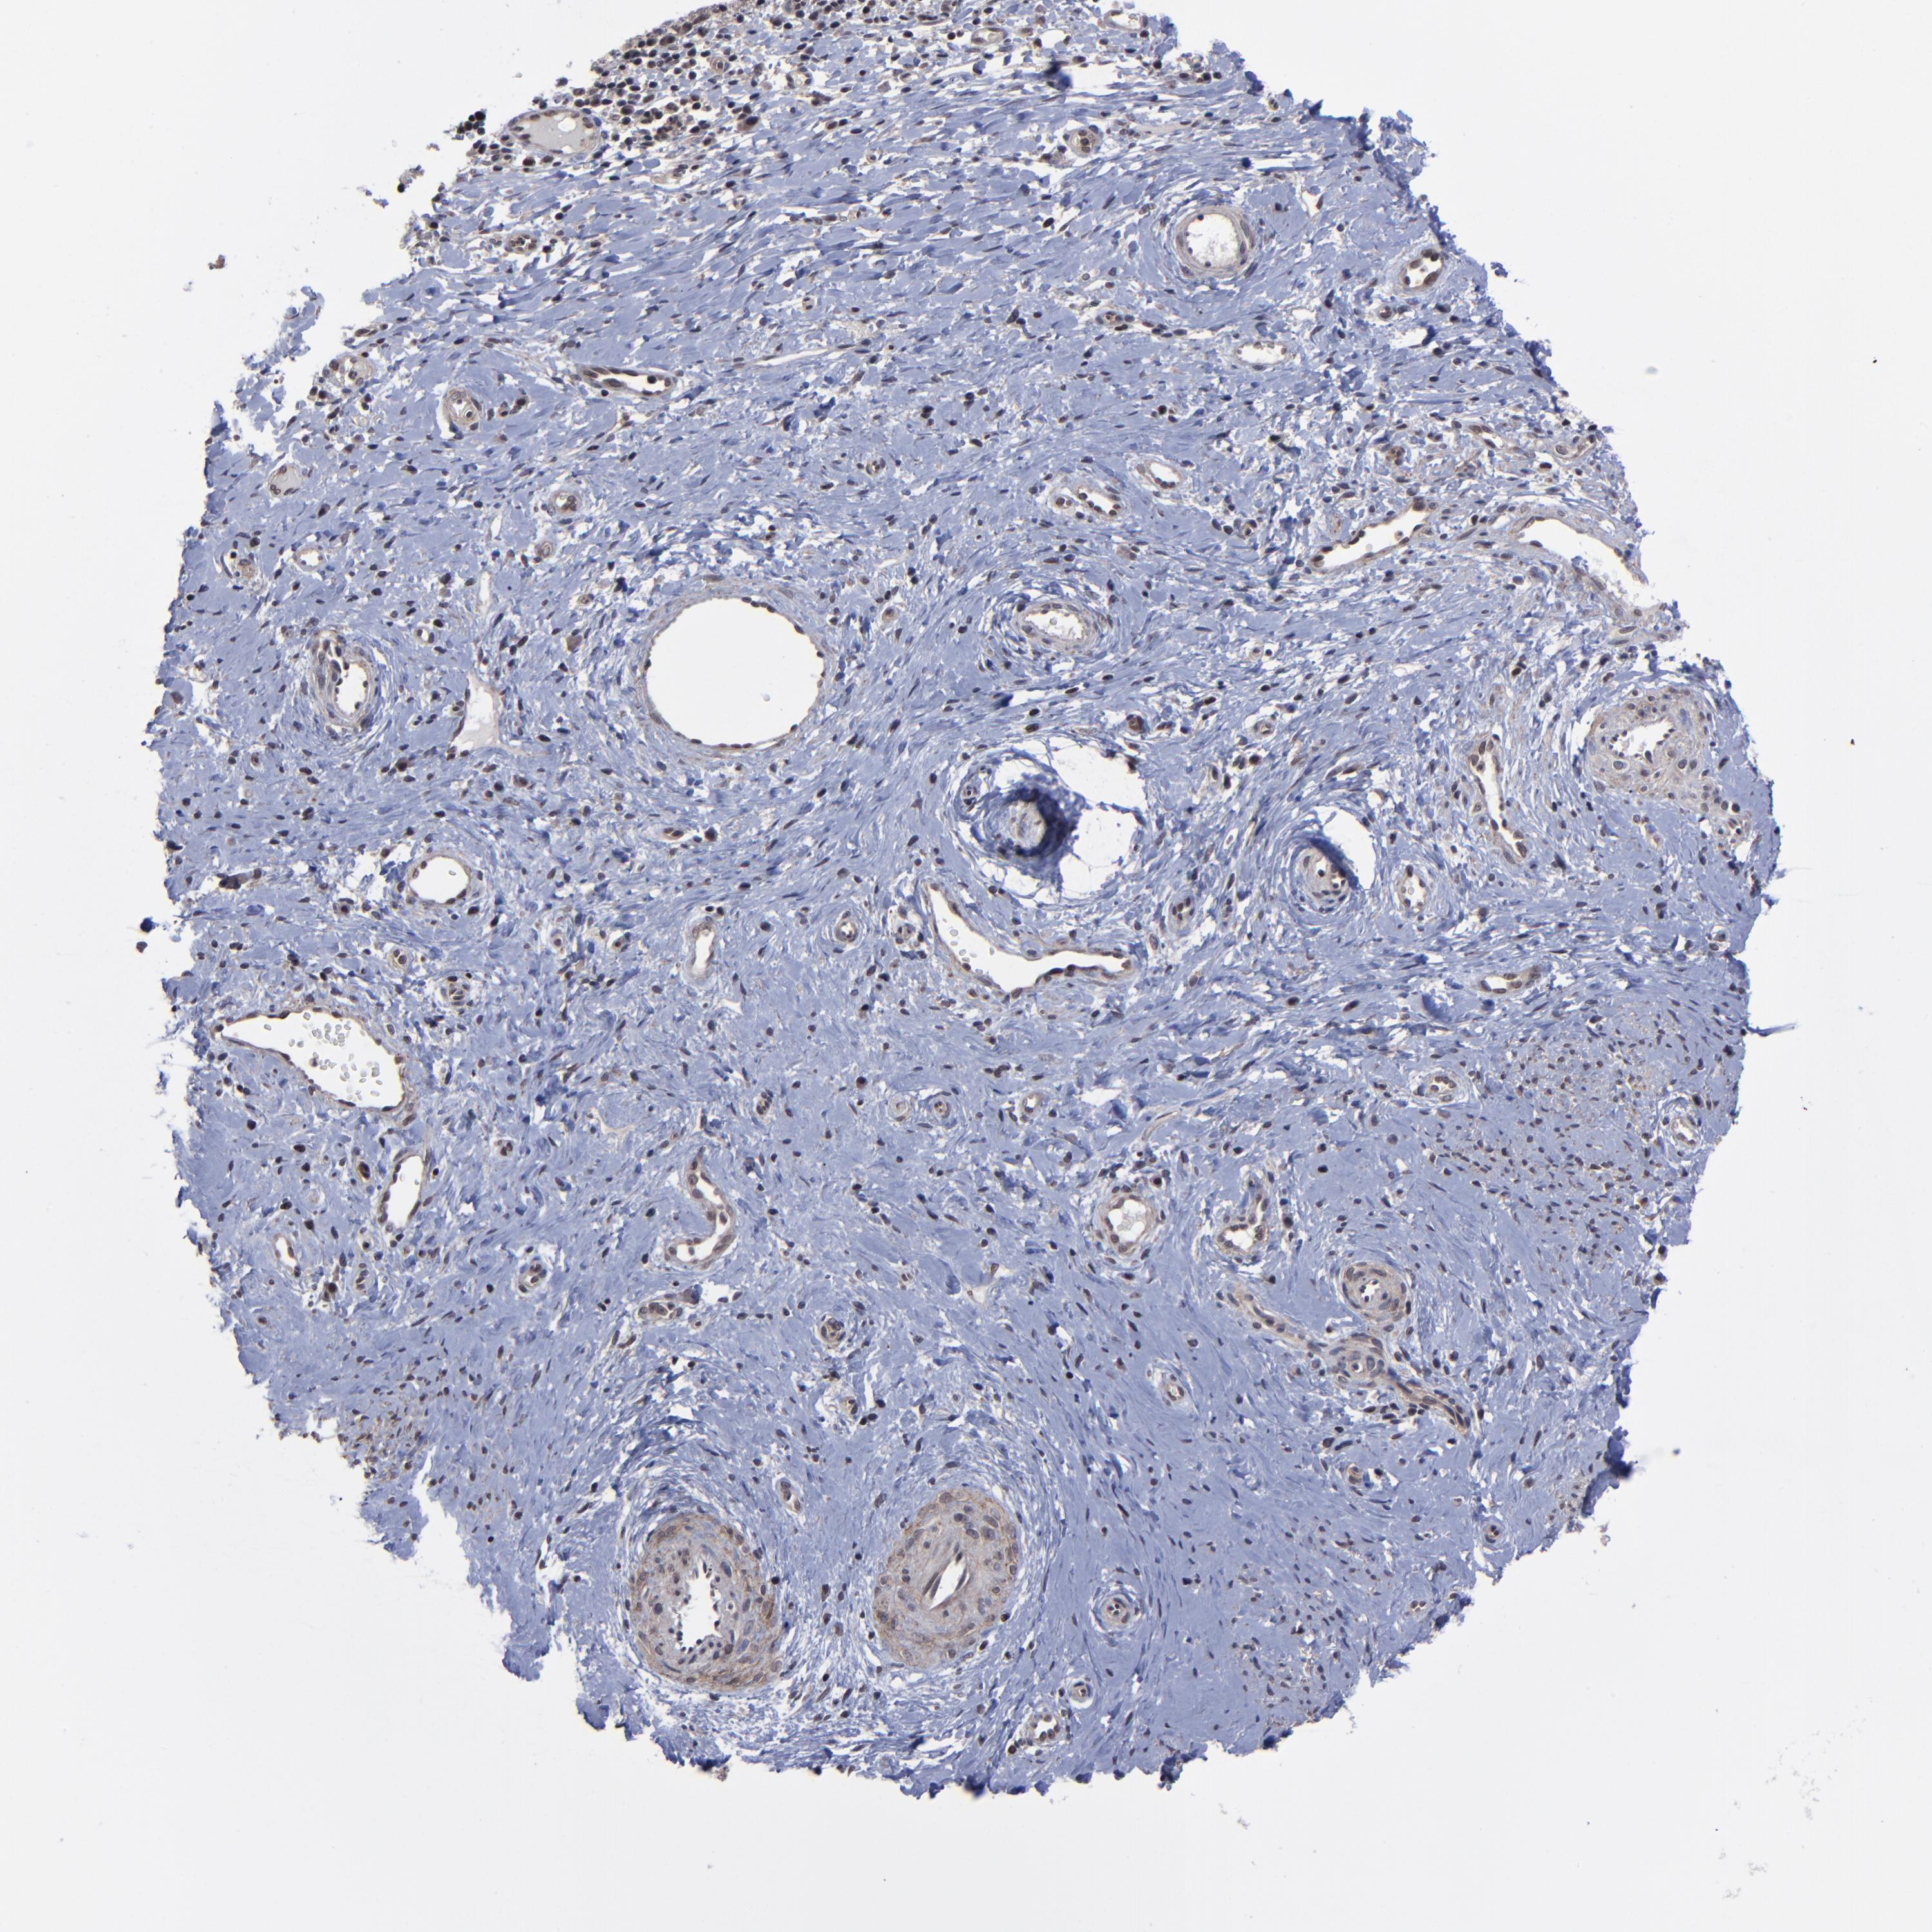

CERVICAL CANCER - Protein expressioni

A mouse-over function shows sample information and annotation data. Click on an image to view it in a full screen mode. Samples can be filtered based on level of antibody staining by selecting one or several of the following categories: high, medium, low and not detected. The assay and annotation is described here.

Note that samples used for immunohistochemistry by the Human Protein Atlas do not correspond to samples in the TCGA dataset.

Antibody stainingi

Antibody staining in the annotated cell types in the current human tissue is reported as not detected, low, medium, or high, based on conventional immunohistochemistry profiling in selected tissues. This score is based on the combination of the staining intensity and fraction of stained cells.

Each image is clickable and will lead to virtual microscopy that enables deeper exploration of all samples and also displays staining intensity scores, fraction scores and subcellular localization as well as patient and tissue information for each sample.

Antibody HPA003152

Antibody HPA003274

Staining

High

Medium

Low

Not detected

Intensity

Strong

Moderate

Weak

Negative

Quantity

>75%

75%-25%

<25%

None

Location

Nuclear

Cytoplasmic/membranous

Cytoplasmic/membranous,nuclear

Squamous cell carcinoma, NOS

Adenocarcinoma, NOS